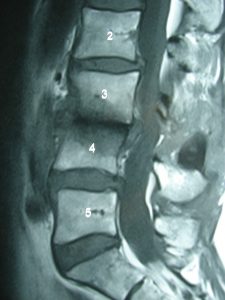

Εικόνα 3 (α,β,γ,δ) MRI – Ο.Μ.Σ.Σ – Ακολουθία Τ1 (α) – Sagittal (β). Εκφύλιση δίσκου Ο3-Ο4 και προβολή του Μεσοσπονδυλίου Δίσκου (Μ.Δ.) όπως και στο επίπεδο Ο2-Ο3 και Ο4-Ο5 που εμφανίζεται ασταθές. Ο δίσκος στο επίπεδο Ο5-Ι1 είναι ακέραιος και δεν υπάρχει αστάθεια.

MRI – Sagittal (γ) Είναι εμφανής η απουσία της σπονδυλικής διάρθρωσης που αφαιρέθηκε στο 1ο χειρουργείο που έγινε στην πάσχουσα για αφαίρεση κήλης Μεσοσπονδυλίου Δίσκου.

MRI – O.M.Σ.Σ. (δ) Παρατηρείται λόγω της αστάθειας έκκεντρη καθίζηση της Ο.Μ.Σ.Σ. στο επίπεδο Ο3-Ο4.